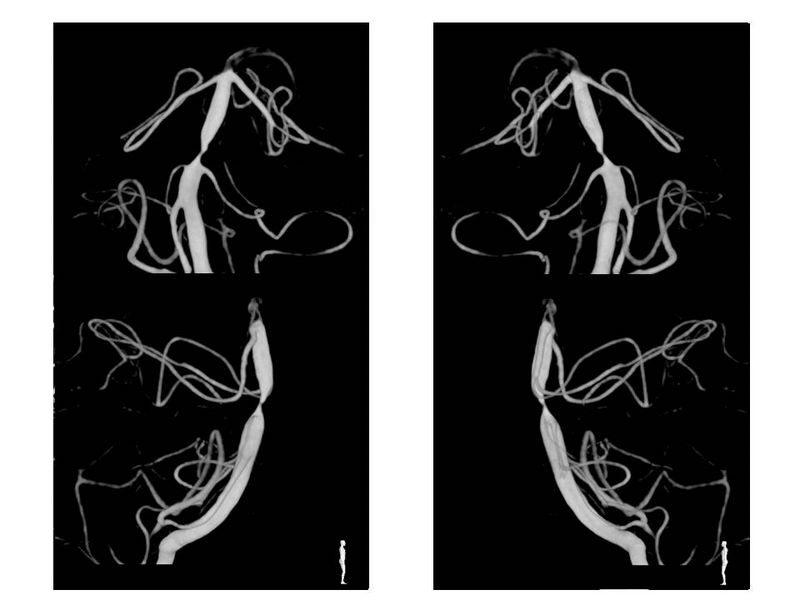

Estenosis Basilar